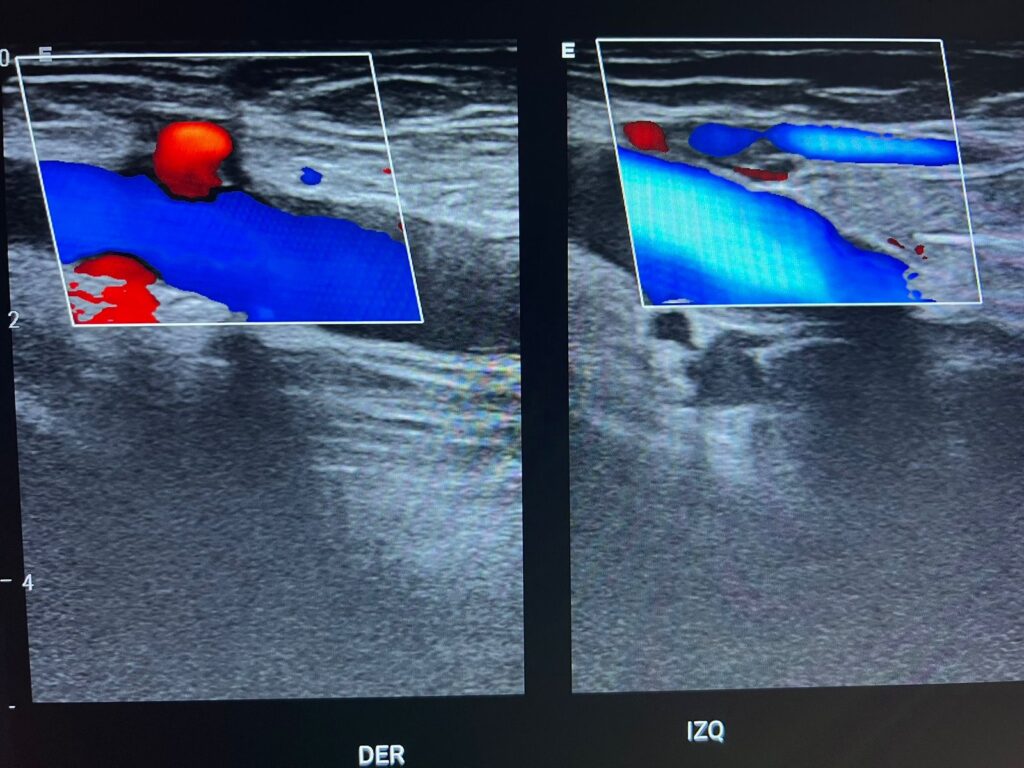

El Hospital Municipal Dr. Luis Espaillat informó la ampliación de sus servicios diagnósticos con la incorporación de la sonografía Doppler, una herramienta de gran importancia para la detección y seguimiento de diversas condiciones de salud relacionadas con la circulación sanguínea.

La dirección del centro de salud detalló que, además del nuevo servicio de Doppler periférico arterial y venoso, así como Doppler carotídeo, el hospital pone a disposición de la comunidad una amplia gama de estudios sonográficos que incluyen: abdominal, obstétrica, ginecológica (transvaginal y suprapúbica), de mama, tiroides, próstata (transrectal y transabdominal), testicular, de partes blandas y músculo esquelético.

Los estudios de Doppler y músculo esquelético estarán disponibles los lunes, miércoles y viernes en horario matutino, mientras que el resto de las sonografías se realizarán todos los días.